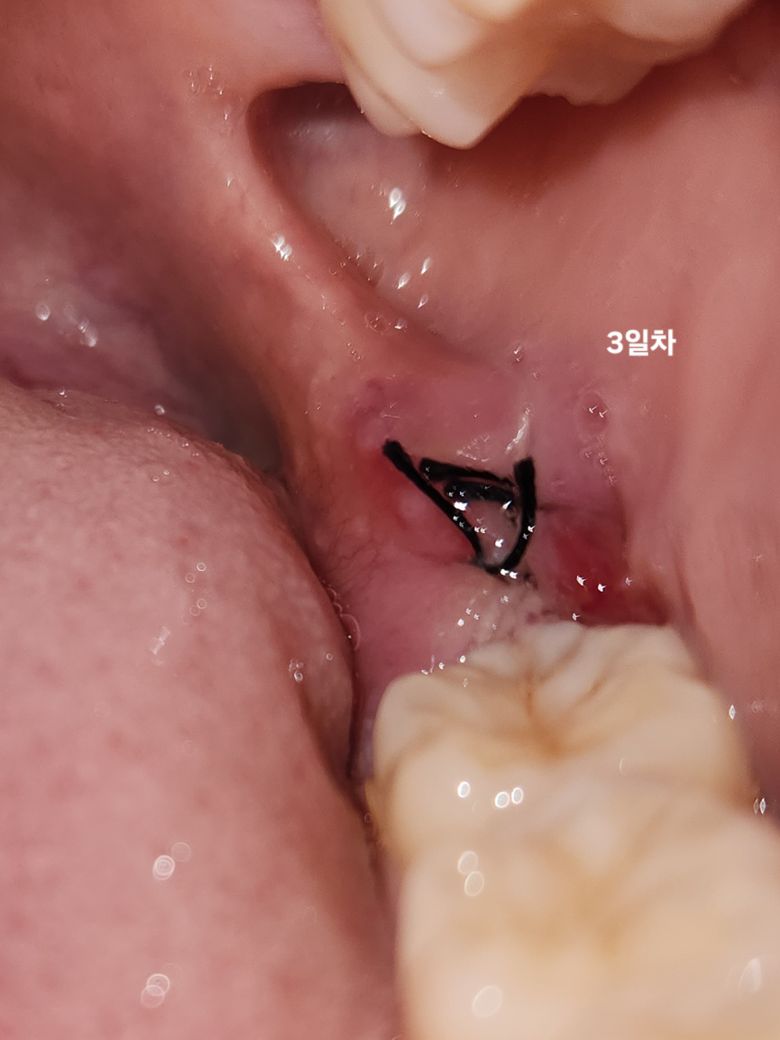

사랑니 발치 4일째인데 드라이소켓인가요?

매복사랑니 발치 한지 4일찬데요 전날(3일차)에는 어금니 바로 뒷쪽에 붙어있던 새살?이 오늘 밥 먹고 보니까 없어지고 틈이 생겼어요ㅠㅠ 그리고 안을 자세히보면 하얀색?이 있는데 잇몸뼈가 드러난걸까요? 이거 드라이소켓인가요ㅠㅠ 오늘 막 발견한거라 그런건지는 몰라도 아직 막 엄청 통증이 있지는 않고 1일차부터 있던 잇몸통이 조금 있어요..ㅠㅠ...

• 1번 째 사진

사진상으로는 크게 문제가 잇어 보이진 않습니다. 하얗게 보이는건 잇몸이 치유되는과정중에 생기는 자연스러운 현상입니다. 아직 잇몸이 다 아물지 않아서 통증이 생긴겁니다.

사진상에서는 특별히 문제가 될만한 부분은 보이지 않습니다. 잘 낫고 있는 것으로 보입니다.

치아를 발치하고 나면 발치한 부위에 하얀색 가피가 형성될수 있습니다.

드라이소켓의 증상은 보이지 않기 때문에 너무걱정하지 않으셔도 될것으로 생각됩니다.

현재 사진상 드라이소켓으로 보이지는 않으며, 경화된 조직 또는 새살로 보입니다. 발치 후 처음에는 이러한 조직이 형성되며, 시간이 지나면서 재생이 이루어집니다. 하지만 하얀색 물질이 단단하고 통증이나 불쾌감이 있다면 감염이 의심되기에 치과진료를 받고 상태를 확인해보길 권합니다.